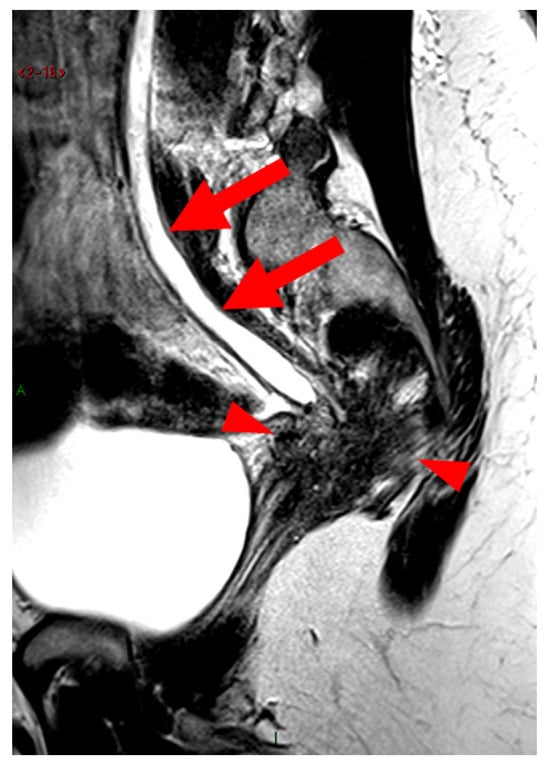

Figure 15. Pelvic MRI scan of a patient with a “kissing ovaries” sign and rectal involvement (i.e., HTD type 6 USLs). (a,b) Axial T2WI (a) and contrast-enhanced T1WI (b) show both ovaries in close proximity (“kissing ovaries” sign) (arrowheads) and rectosigmoid wall infiltration (arrows). (c) Sagittal contrast-enhanced T1WI shows rectosigmoid wall infiltration, appearing as a “medallion-shaped” lesion outlined by markedly enhancing mucosa (arrowhead).

2.3.1. “Kissing Ovaries”: A Form Straddling Between Type 5B and Type 6 USLs

Besides endometriomas, another type of ovarian involvement in DIE includes adhesions that cause the ovaries to retract medially across the midline, behind the uterus, into the pouch of Douglas. When the ovaries are displaced medially and are in close proximity, they are commonly referred to as “kissing ovaries”. Additionally, medialized ovaries on preoperative imaging expose the digestive tract to a 20% risk of involvement [22]. In our experience, the injection of a contrast agent is useful when there is doubt about an endometriotic rectosigmoid invasive lesion on T2WI, especially if a rectal filling was not performed. A markedly enhancing mucosa, which outlines rectosigmoid local wall thickening on post-contrast T1WI without fat suppression (forming a “medallion-shaped” lesion), is a valuable aid to diagnosis.

In the HTD MRI classification of USLs, the “kissing ovaries” sign is considered a form between types 5B and 6. In the case of concomitant rectal involvement, the USL is classified as type 6 (Figure 15); otherwise, it is classified as type 5B (comparable to a nodule with spiculated margins).